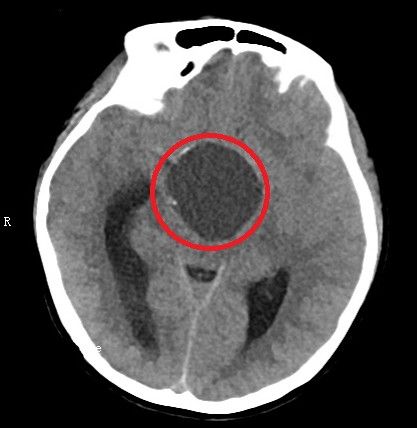

术前头部ct和核磁共振检查显示:鞍区肿瘤(红圈内)比乒乓球还大,并压迫周围重要的神经和血管。

入院后进一步检查发现,肿瘤约为4.5×4.4×4.6cm,比乒乓球还大,周围遍布颈内动脉、视神经、三脑室底、海绵窦、垂体、垂体柄等重要的神经和血管。医生告诉小雯和家属,由于肿瘤压迫视神经,因此导致她视力减退;还压迫垂体,导致其内分泌紊乱、月经失调,并形成颅高压。如不尽快手术,病情继续进展可能危及生命。